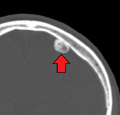

Osteoma of the frontal sinus on CT

Osteoma represents the most common benign neoplasm of the nose and paranasal sinuses. The cause of osteomata is uncertain, but commonly accepted theories propose embryologic, traumatic, or infectious causes. Osteomata are also found in Gardner's syndrome. Larger craniofacial osteomata may cause facial pain, headache, and infection due to obstructed nasofrontal ducts. Often, craniofacial osteoma presents itself through ocular signs and symptoms (such as proptosis).[1]